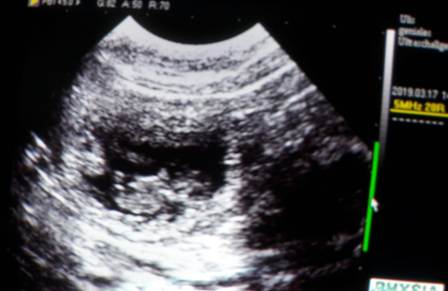

Ich konnte mich nicht zurückhalten und musste heute noch einmal nachsehen :)

Franzi und ich haben viele Fruchtblasen, muntere Babys und schlagende Herzchen gesehen!

Zählen war unmöglich, wie ihr auf dem dritten Bild sehen könnt,

haben sich manchmal an einem Platz fünf Fruchtblasen geöffnet :O

Oft lagen zwei dicht nebeneinander, wie auf dem letzten..

Wir sind sehr gespannt!!!